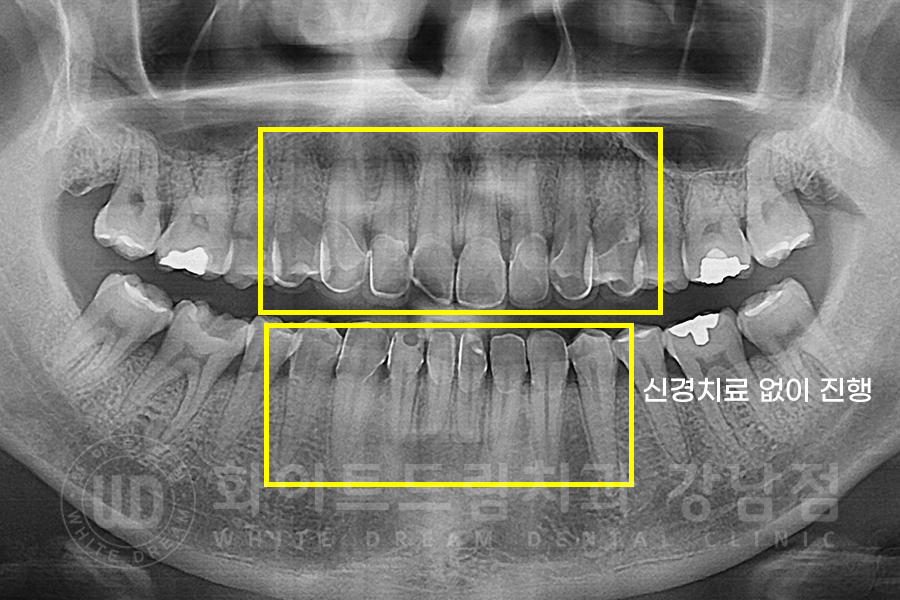

▲ 환자분의 치료 후 x-ray 사진입니다.

자연치아를 최대한 적게 삭제하여 진행하였고, 신경관 노출도 되지 않아 신경치료 없이 자연스럽게 마무리가 되었습니다.

당일 보철 부착을 말씀드렸는데, 환자분의 개인적인 시간상 불가능하여

일주일 뒤 다시 내원하셔서 최종 라미네이트를 부착하고 치료는 종료되었습니다.